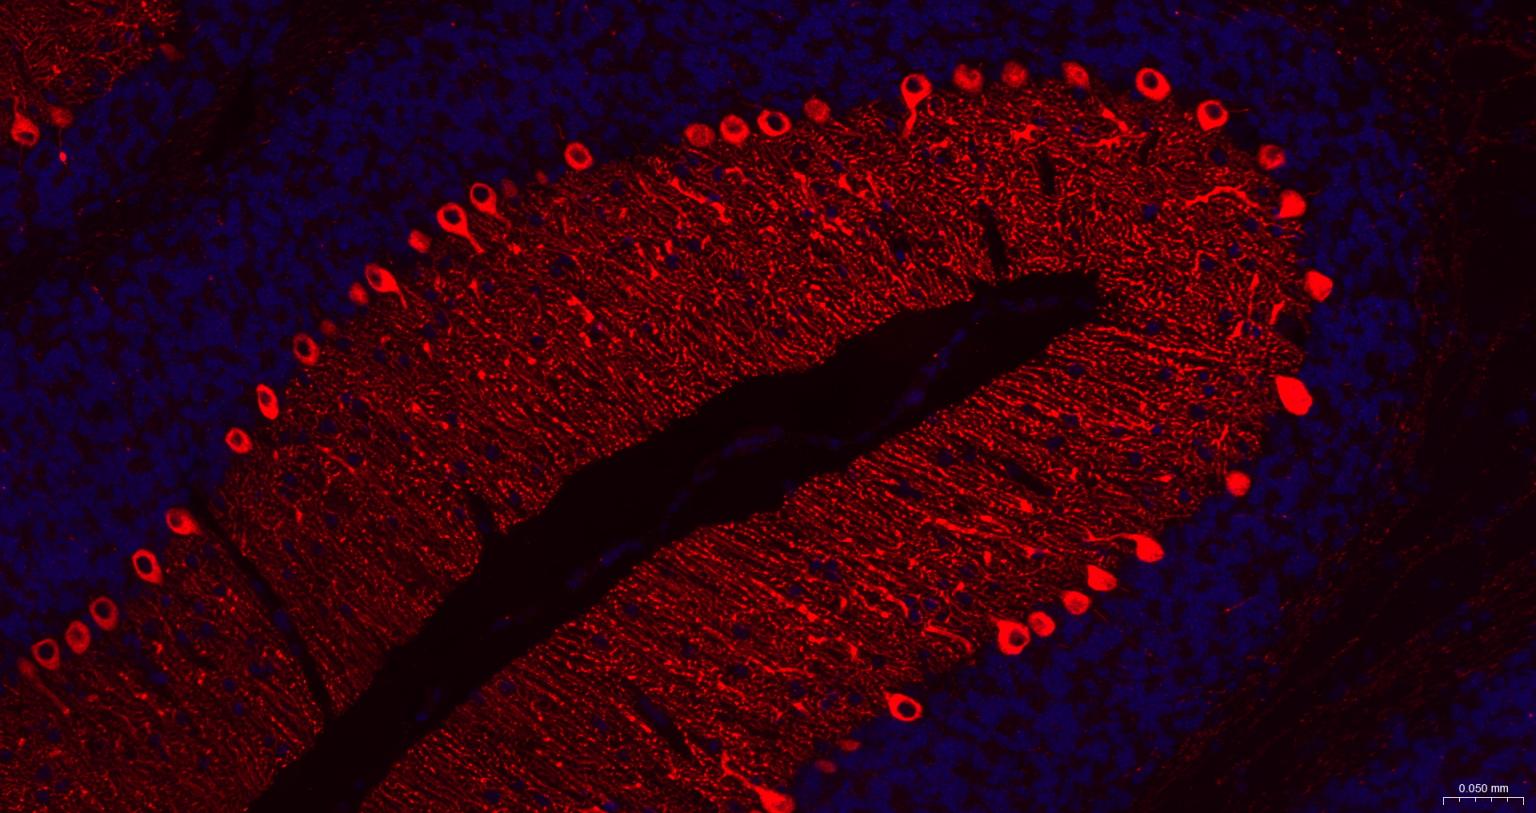

Paraformaldehyde-fixed, paraffin embedded Human Cerebellum; Antigen retrieval by boiling in sodium citrate buffer (pH6.0) for 15 min; The section was incubated with IP3 Monoclonal Antibody, Unconjugated (bsm-61555R) at 1:200 overnight at 4°C. Followed by conjugated Goat Anti-Rabbit IgG antibody (Red, bs-0295G-BF594), DAPI (blue, C02-04002) was used to stain the cell nuclei.

Paraformaldehyde-fixed, paraffin embedded Mouse Cerebellum; Antigen retrieval by boiling in sodium citrate buffer (pH6.0) for 15 min; The section was incubated with IP3 Monoclonal Antibody, Unconjugated (bsm-61555R) at 1:200 overnight at 4°C. Followed by conjugated Goat Anti-Rabbit IgG antibody (Red, bs-0295G-BF594), DAPI (blue, C02-04002) was used to stain the cell nuclei.

Paraformaldehyde-fixed, paraffin embedded Rat Cerebellum; Antigen retrieval by boiling in sodium citrate buffer (pH6.0) for 15 min; The section was incubated with IP3 Monoclonal Antibody, Unconjugated (bsm-61555R) at 1:200 overnight at 4°C. Followed by conjugated Goat Anti-Rabbit IgG antibody (Red, bs-0295G-BF594), DAPI (blue, C02-04002) was used to stain the cell nuclei.